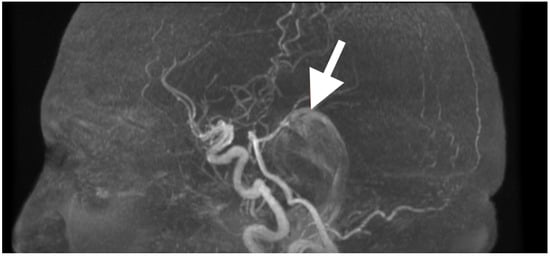

Background and Clinical Significance: Fourth ventricular epidermoid cysts are among the least frequently encountered intracranial tumors (less than 1%). Their slow growth pattern along cisternal and subarachnoid spaces, and their close proximity to neurovascular structures (brainstem–cerebellar), create difficulty for surgical treatment. Total removal is often complicated by the capsule’s adherence to eloquent structures and requires a thoughtful surgical approach of weighing radical resection versus neurologic/function preservation. This case description provides an example of using careful clinical–radiological correlation and anatomy-dissecting microsurgery as a method of permanent decompression and neurologic recovery with low operative risk. Case Presentation: A 57-year-old female presented with impaired stability of gait, gaze-evoked nystagmus, appendicular ataxia, minimal ipsilateral hypotonia, and mild bulbar dyscoordination. Imaging (MRI, MRA) revealed a large, lobulated mass that was lobulated and avascular centered in the left cerebellar hemisphere, with an extension into the vermis and cisterna magna, and partial filling of the fourth ventricle with classic epidermoid imaging. Resection was performed via a midline suboccipital telovelar approach with microsurgery, relying on native arachnoid planes and quadrant opportunities of decompression, while preserving critical neurovascular structures. A thin rim of capsule intimately adherent to the floor of the ventricle was intentionally left to minimize irreversible cranial nerve injury. Histology showed keratinizing stratified squamous epithelium with laminated keratin and cholesterol clefts. Following resection, truncal stability, limb coordination, and ocular pursuit improved without additional deficits. Initial and 3-month postoperative MRI showed total decompression, re-established CSF pathways, and no recurrence. Conclusions: This case demonstrates that maximal safe resection (with function preservation) through natural anatomy corridors can achieve excellent neurologic results in fourth ventricular epidermoids. Lifelong MRI surveillance will be needed due to the srisk of delayed recurrence even after near-total resection. Full article

Figure 1